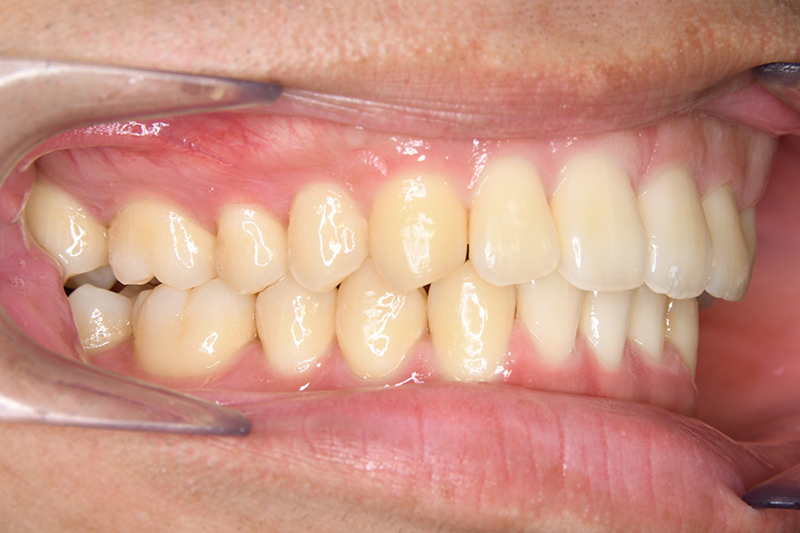

動的治療終了時

FP・IOP

批評・予后 左側臼歯uprightによって鋏状咬合、過蓋咬合の改善が得られた。下顎前歯先欠によるAnterior ratio不調和と上顎前歯部叢生の改善を目的とし、上顎前歯にIPRを行ったが、治療後において左上2付近のover jetが大きく、上顎犬 歯間幅径の拡大(1.5mm)も生じているため、後戻りの懸念が残る。口元や歯列の安定性を考慮し、小臼歯抜歯も検討したがハイアングルであり下顎3-incisalのため、治療が困難となる事を危惧して非抜歯にて治療を行った。